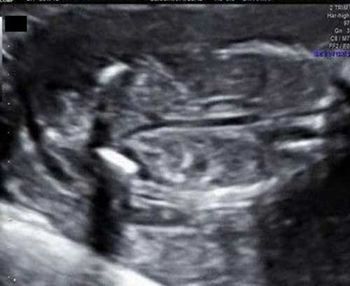

QUIZ: What's causing the compression of the fetal heart (tubular shaped), ascites and dilated trachea?